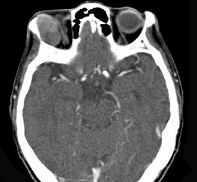

辅助检查中最有意义的发现是(如图)()

-